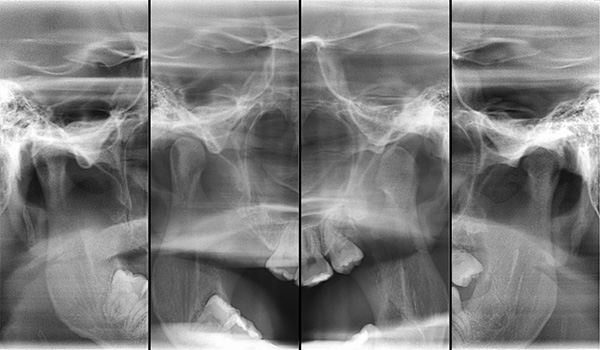

Dos métodos diagnósticos adicionais, os exames radiológicos são obrigatórios:

- Um raio-x da ATM na boca aberta e fechada do paciente é realizado pelo médico para garantir que a articulação temporomandibular não seja a causa da mordida cruzada.